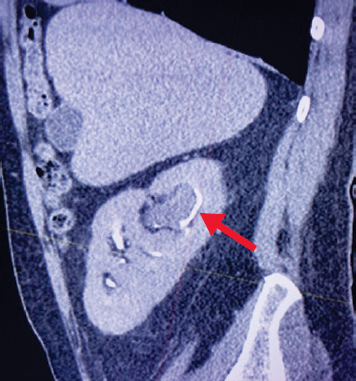

В СПб ГБУЗ «Клиническая больница Святителя Луки» в январе 2019 г. обратился пациент 73 лет с жалобами на гематурию и тупые тянущие боли в левой поясничной области. Из анамнеза известно, что в 2006 г. была выполнена нефрэктомия слева по поводу почечно-клеточного рака pT2aNoMo. По данным магнитно-резонансной томографии с внутривенным контрастированием выявлена опухоль лоханки единственной правой почки размером до 35 мм (рис. 1). Учитывая локализацию, размер опухоли и наличие единственной правой почки, пациенту в качестве нефронсохраняющей методики была выполнена перкутанная лазерная резекция опухоли.

Рис. 1. Магнитно-резонансная томография. Опухоль лоханки правой почки (указана стрелкой)

Fig. 1. Magnetic resonance imaging. Tumor on the right kidney pelvis (indicated by an arrow)